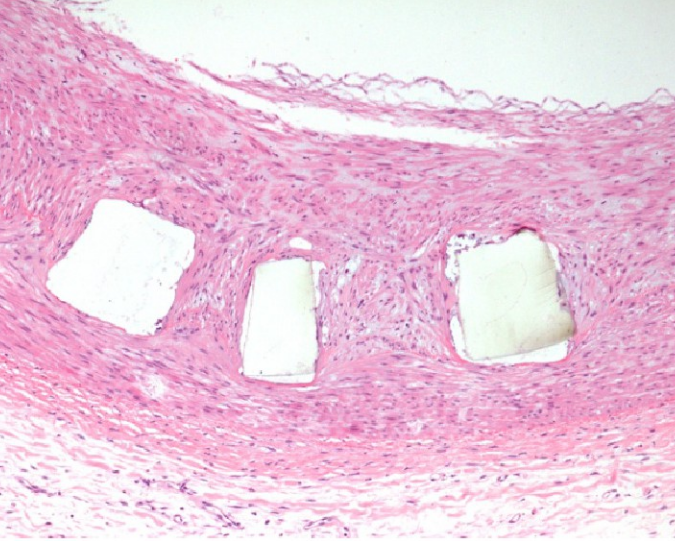

植入7天后显微观察显示,支架杆周围仅存在微量血栓附着。28天时血栓开始被肉芽组织包裹,90天后实现完全吸收且无新血栓生成,证明材料具有渐进式内皮修复特性。

图1. 7d

图2. 28d

图3. 90d